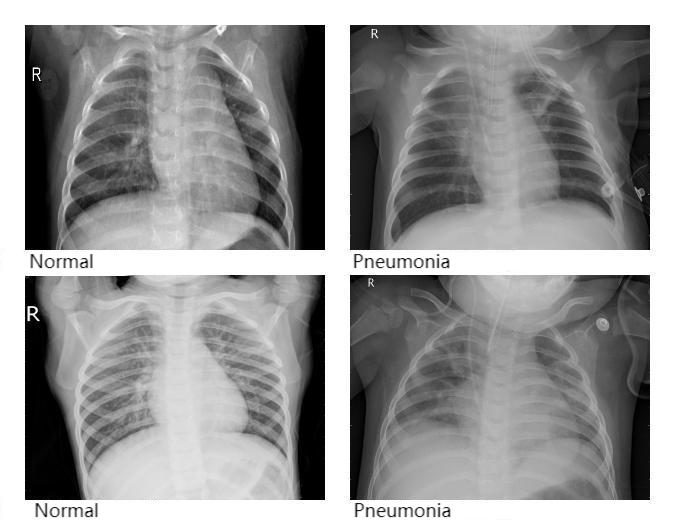

Pneumonia Detection and Analysis Using AlexNet

Because pneumonia incidence remains high and traditional diagnostic methods face efficiency bottlenecks, and since convolutional neural networks are increasingly applied in medical image analysis, this paper employs the AlexNet model to analyze chest X-ray images for pneumonia detection. The study optimizes the training process by tuning the number of epochs to identify the model with the best accuracy. Experimental results show that the model achieved an accuracy of 0.8108 (81.08%), demonstrating good capability for recognizing pneumonia in X-ray images. This method can help reduce the bias and time required by manual interpretation, effectively improve the efficiency of pneumonia screening, and gain valuable time for timely diagnosis and treatment.